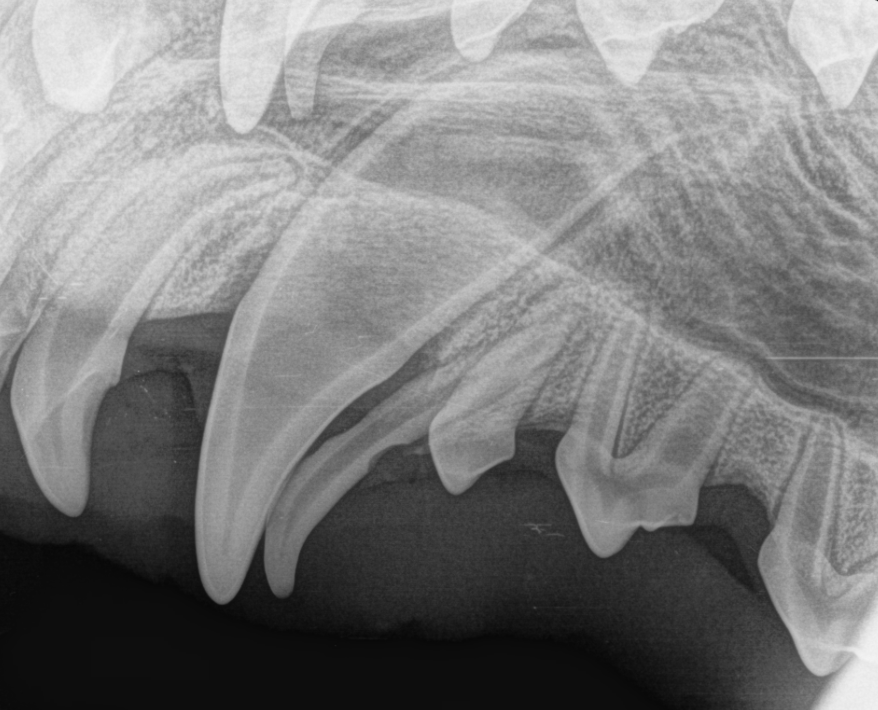

Vi tok røntgen både før og etter inngrepet for å sikre at alt var fjernet og at de permanente tennene ikke var skadet. Til slutt ble tannkjøttet sydd.

Hos Chicco satt melketennene helt fast og var ikke til å rikke. Siden han var seks måneder gammel, ble det besluttet å trekke dem.

Chicco ble lagt i full narkose og fikk både lokalbedøvelse og god smertelindring. Under inngrepet åpnet vi tannkjøttet og fjernet noe av tannbeinet for å få ut hele tannen med roten.